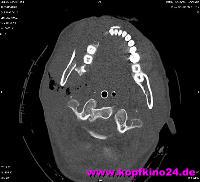

Zur genauen Planung der Kieferkorrektur wurde ich zum CT geschickt. Aus den scheibchenweisen Bildern setzte der Computer ein dreidimensionales Bild zusammen. Dabei ist auch sehr deutlich dieses verlagerte Knochenstück zu sehen.

Zwischenzeitlich stand auch mal die Überlegung im Raum, eine Kinnplastik durchzuführen, bei der die Kinnspitze abgesägt und danach im "richtigen" Winkel wieder aufgesetzt wird. Das klang natürlich auch erst mal ein bissel erschreckend - aber schließlich zählt das Ergebnis. Nach Auswertung der 3-D-Annimation wurde dann allerdings "nur" die erstbeschriebene Kieferkorrektur durchgeführt.